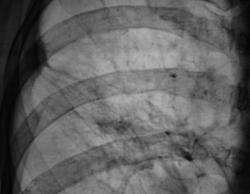

После расшифровку флюорограмм пациента "взяли на контроль". Произведена рентгенография в прямой и правой боковой проекциях.

Всё же я отдал бы предпочтение посттуберкулёзному утолщению плевры, это подкрепляется наличием множества кальцинатов и интесивность тяжестости характерна для фиброза, но ни как для лимфангиита. В большинстве случая имеет место быть выпоту в плевральной полости. Но верификация конечно должна быть на уровне гистологии если есть подозрение.

Пациент, когда-то состоял на учете у фтизиатра, проводилось специфические лечение, хотя - "концов нет". Не нашли ни снимки и карточки. Дело в том, что раньше при ЛПУ было туб. отделение, которое было ликвидировано несколько лет назад, и в процессе ликвидации ликвидировались....

Склоняюсь к посттуберкулезным изменениям. Вероятно очаг был в 3-м сегменте и прилежал к междолевой плевре, отсюда и изменения самой плевры в виде спаек.